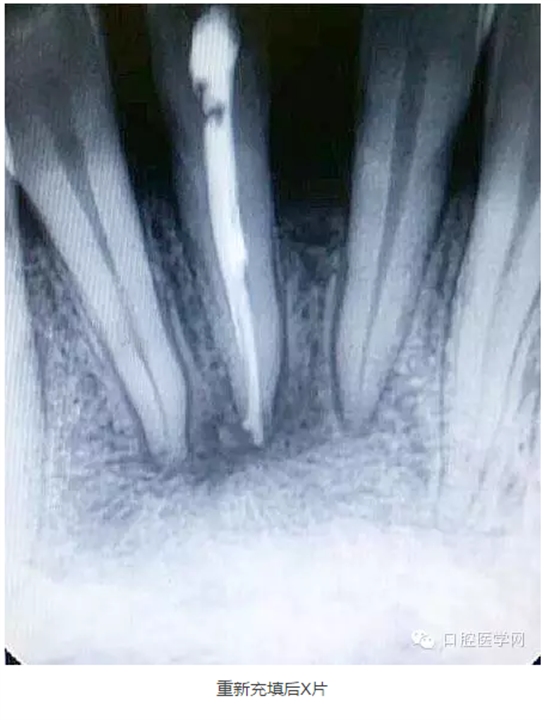

9.觀察一個月后打開暫封物拔出牙膠尖,檢查根管內(nèi)是否有滲出液,如果根管基本干燥,可再次沖洗消毒后根充,仍有滲出液者應(yīng)查明情況繼續(xù)治療。

下面是一例 今年年初治療的下前牙根尖囊腫病例,患者因故未能按時復(fù)診,最近才來。